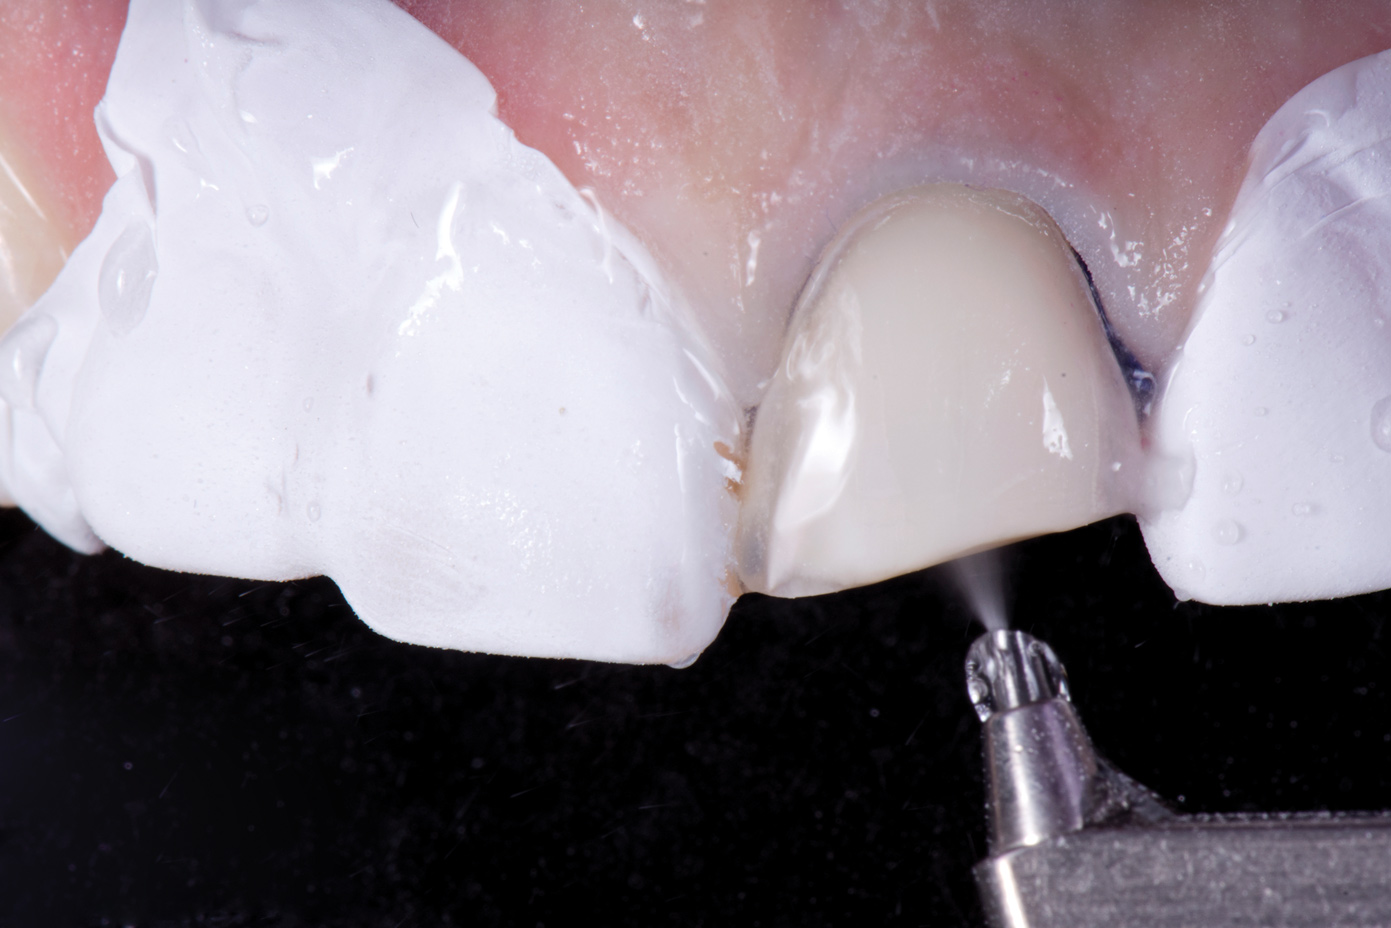

Air abrasion with aluminum trihydroxide has been used as an adjunctive for tooth preparation to remove plaque, light calculus, undermined enamel, poorly bonded resins or liners, and soft-tissue tags prior to bonding. The rationale of biofilm removal before bonding is to remove any impediments to effective etching of enamel that may lead to reduced bond strength and microgaps that could contribute to future stain and leakage. Because biofilm can be difficult to visualize, a one-time application of a two-tone disclosing solution to dried teeth may help reveal biofilm and provide a visual cue for effective removal (Figure 17 through Figure 19). Some cleaning particles other than glycine or sodium bicarbonate can alter the enamel surface; therefore, reapplication of disclosing solution should be avoided as this may lead to risk of undesired staining of tooth structure.

Fig 17. Application of two-tone disclosing solution to reveal biofilm.

Fig 18. Air abrasion with aluminum trihydroxide to remove biofilm.

Fig 19. Cleaned tooth surfaces after air abrasion prior to application of adhesive bonding resin composite to close black triangles.